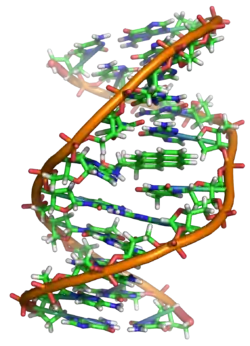

Smoke contains several carcinogenic pyrolytic products that bind to DNA and cause genetic mutations. Particularly potent carcinogens are polycyclic aromatic hydrocarbons (PAH), which are toxicated to mutagenic epoxides. The first PAH to be identified as a carcinogen in tobacco smoke was benzopyrene, which has been shown to toxicate into an epoxide that irreversibly attaches to a cell's nuclear DNA, which may either kill the cell or cause a genetic mutation. If the mutation inhibits programmed cell death, the cell can survive to become a cancer cell. Similarly, acrolein, which is abundant in tobacco smoke, also irreversibly binds to DNA, causes mutations and thus also cancer. However, it needs no activation to become carcinogenic.[220]

- Polycyclic aromatic hydrocarbons are tar components produced by pyrolysis in smoldering organic matter and emitted into smoke. Several of these PAH's are already toxic in their normal form, however, many of then can become more toxic to the liver. Due to the hydrophobic nature of PAH's they do not dissolve in water and are hard to expel from the body. In order to make the PAH more soluble in water, the liver creates an enzyme called Cytochrome P450 which adds an additional oxygen to the PAH, turning it into a mutagenic epoxides, which is more soluble, but also more reactive.[222] The first PAH to be identified as a carcinogen in tobacco smoke was benzopyrene, which been shown to toxicate into a diol epoxide and then permanently attach to nuclear DNA, which may either kill the cell or cause a genetic mutation. The DNA contains the information on how the cell function; in practice, it contains the recipes for protein synthesis. If the mutation inhibits programmed cell death, the cell can survive to become a cancer, a cell that does not function like a normal cell. The carcinogenicity is radiomimetic, i.e. similar to that produced by ionizing nuclear radiation. Tobacco manufacturers have experimented with combustion less vaporizer technology to allow cigarettes to be consumed without the formation of carcinogenic benzopyrenes.[223] Although such products have become increasingly popular, they still represent a very small fraction of the market, and no conclusive evidence has shown to prove or disprove the positive health claims.

The carcinogenity of tobacco smoke is not explained by nicotine per se, which is not carcinogenic or mutagenic, although it is a metabolic precursor for several compounds which are. In addition, it inhibits apoptosis, therefore accelerating existing cancers.[252] Also, NNK, a nicotine derivative converted from nicotine, can be carcinogenic.